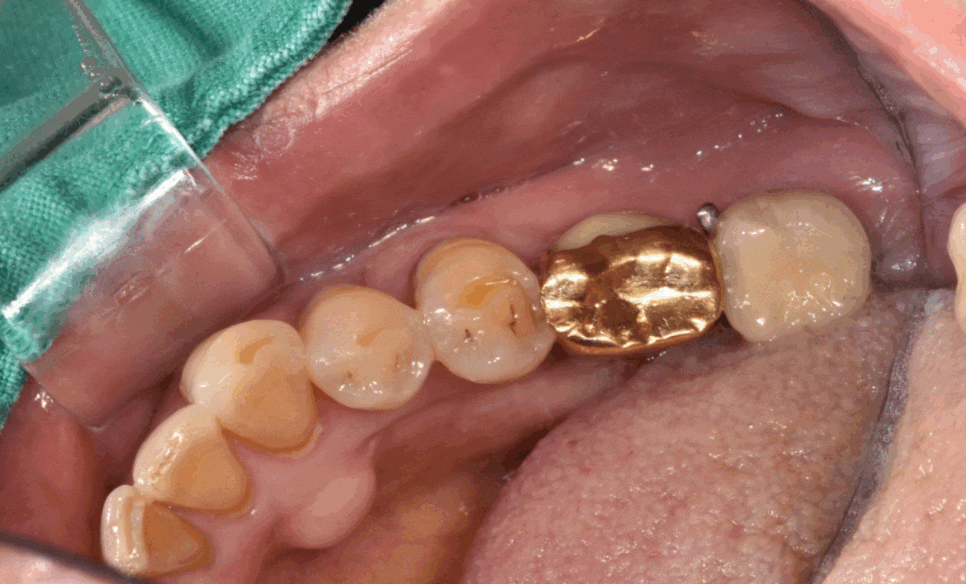

24년 1월 26일 환자분을 처음 만나게 되었습니다.

24.01.26

한눈에 보기에도 으스러진 치아들 ㅠㅠ